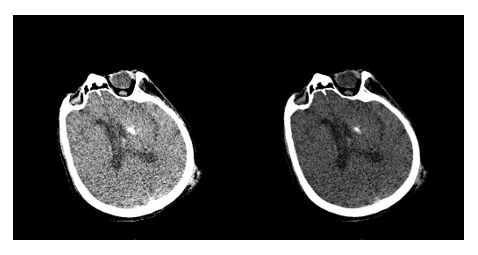

Thanks to these reconstructions (Figure 1), it was possible to identify a subdural hemorrhage of approximately 1.9 mm × 21.4 mm, which, due to its proximity to the bony tissue of the cranial vault, would not have been visible otherwise.

Figure 1. (Left) Reconstruction on the coronal plane of the brain with magnifying glass on the identified lesion. (Center) Reconstruction on the coronal plane of the brain with magnifying glass and color inversion to better visualize the hemorrhage. (Right) Reconstruction on the sagittal plane of the brain and the identified hemorrhage.